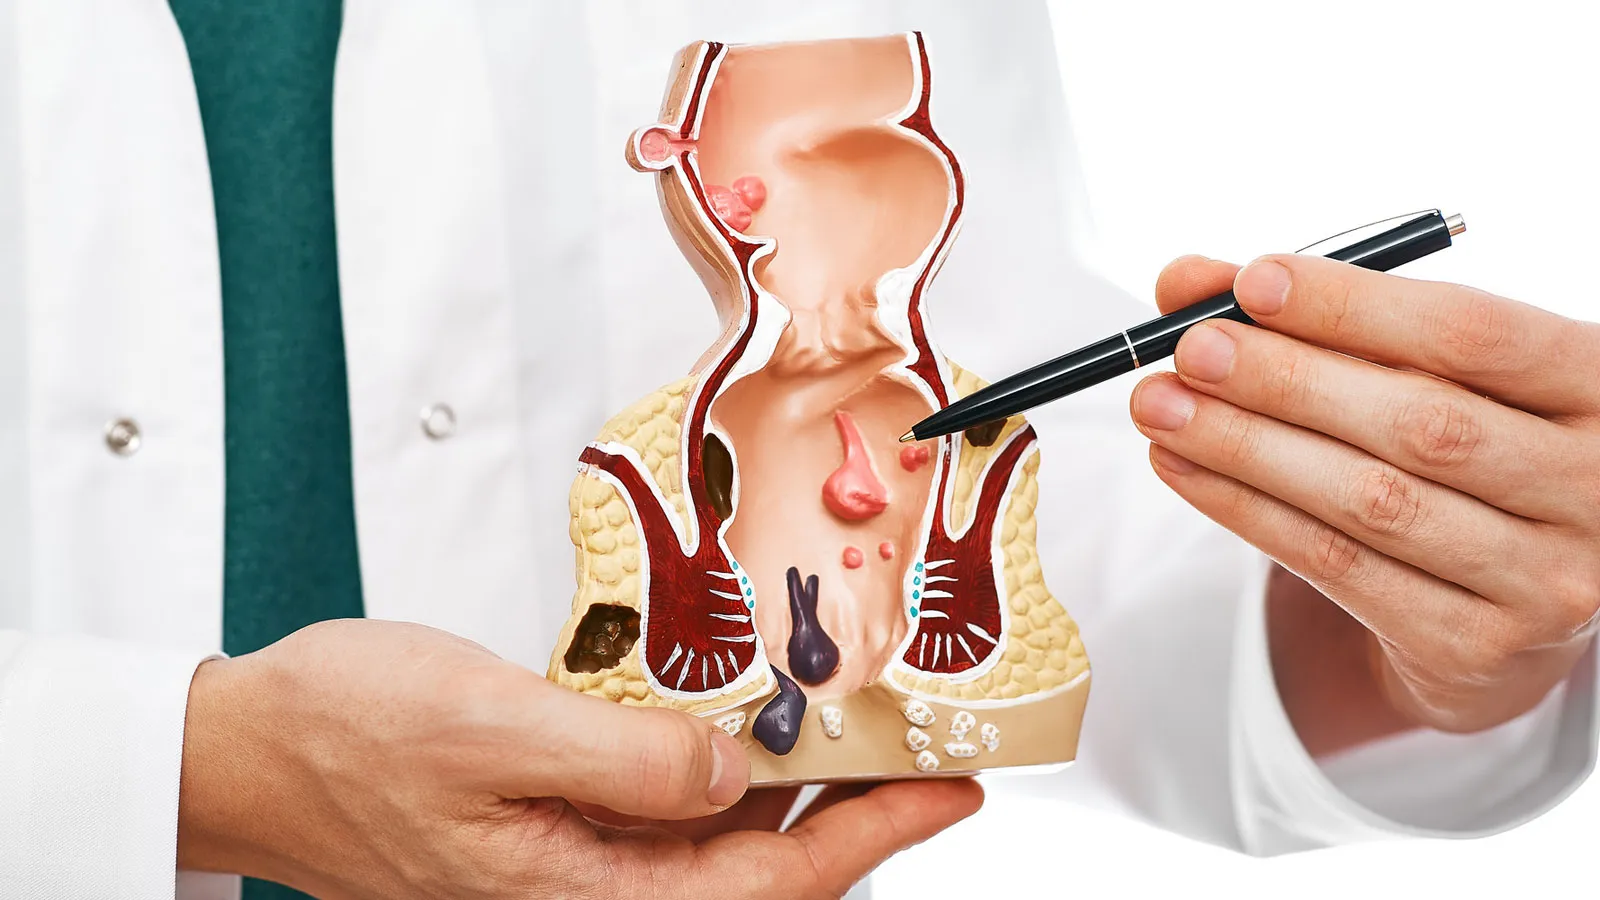

An anorectal abscess is a painful collection of pus near ...

Have you undergone surgery for an anal ..

If you have been dealing with pain, swelling, or pus near the anus that keeps coming back ...

At Karan Hospital, understanding your condition is the first step to better ...